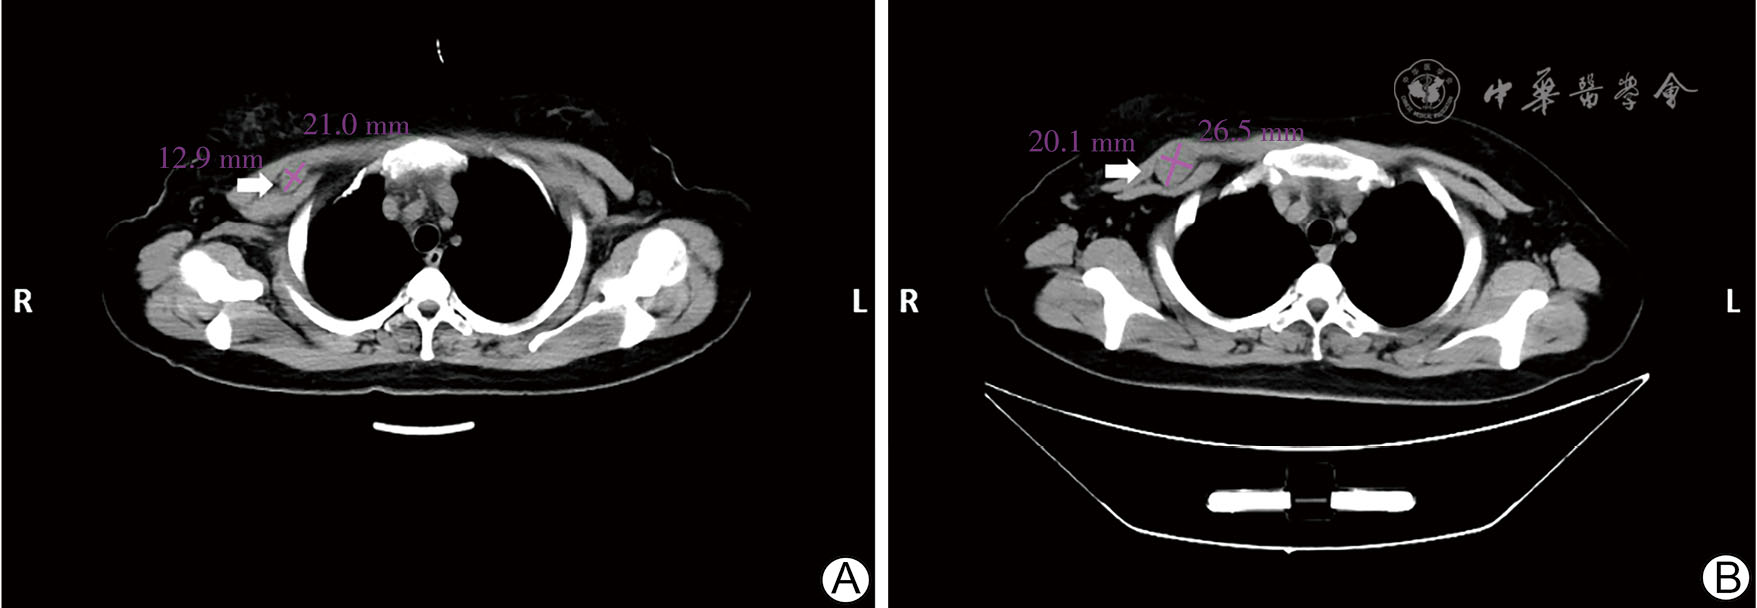

图2 三阴性乳腺癌患者新辅助化疗中断保肝治疗期间与术前右乳肿瘤胸部CT表现 A图为保肝治疗期间;B图为术前,可见右乳肿块较前明显增大 注:箭头示右乳肿瘤

图3 三阴性乳腺癌患者新辅助化疗中断保肝治疗期间与术前胸肌间淋巴结胸部CT表现 A图为保肝治疗期间;B图为术前,可见右侧腋窝胸肌间淋巴结较前增大 注:箭头示右侧腋窝胸肌间淋巴结